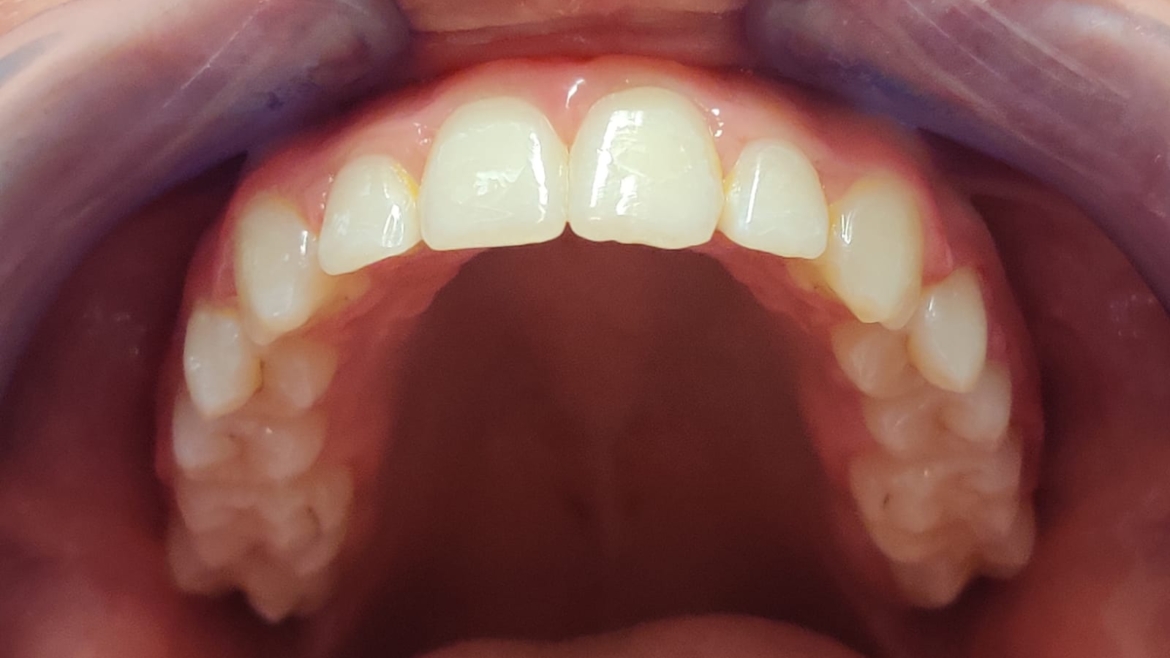

Paziente affetto da malocclusione di II classe, I divisione, caratterizzata da overjet aumentato e morso profondo (deepbite). Il trattamento è stato eseguito con terapia ortodontica fissa multibrackets, durata complessiva 12 mesi.

Il trattamento ha consentito il ripristino dell’equilibrio occlusale e un significativo miglioramento sia funzionale che estetico, senza necessità di estrazioni o ausili extraorali.